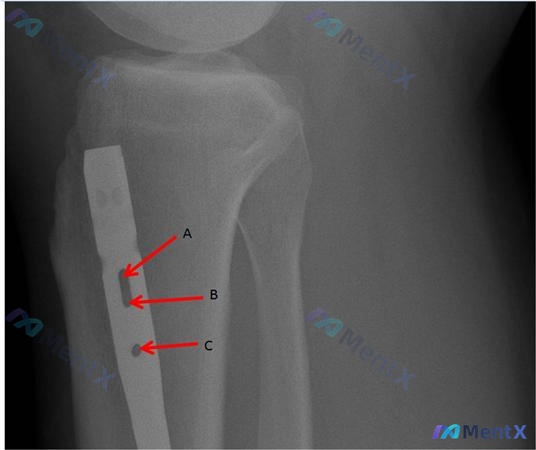

基本情况:27岁男性,接受髓内钉固定的中轴胫骨骨折(近端、远端均做了静态锁定)。

临床问题:术后3个月复查发现只有极少量骨愈合,临床决定转为「动力化」固定。

核心疑问:如果有标注A、B、C的锁钉孔,互锁螺钉应该怎么调整?

📋答案:正确答案为:仅近端静态锁孔(A位)。动力化核心是解除近端刚性固定,保留远端锁钉维持旋转稳定,通过负重时轴向微动刺激骨痂形成。